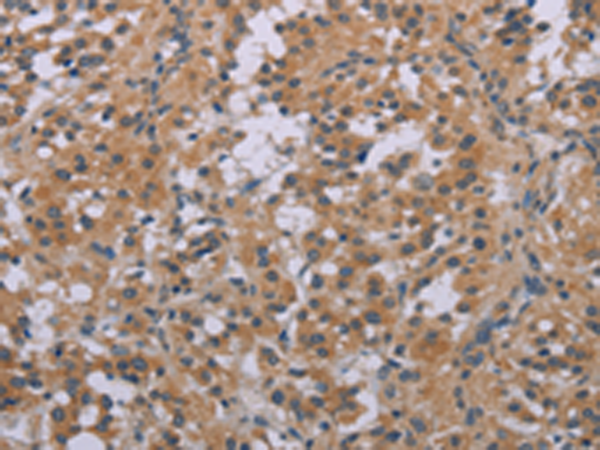

IHC positive control: |

Human thyroid cancer and Human brain |

IHC Recommend dilution: |

25-100 |